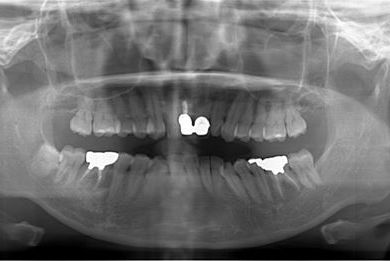

インプラント治療+セラミック治療

| 性別/年齢 | 女性 / 42歳 | ||||||||||||||||||||||||||||||||

| 主訴 | 別の病院で、右奥歯の根の部分にインプラント治療が必要と言われたので、セカンドオピニオンを希望。 | ||||||||||||||||||||||||||||||||

| 治療方針 | 右下奥、保存不能の歯を抜歯し、インプラント治療にて、機能的・審美的回復を行う。 | ||||||||||||||||||||||||||||||||

| 治療内容 | インプラント1本、メタルボンドセラミッククラウン2本(メタルボンド用土台1本) | ||||||||||||||||||||||||||||||||

| 総治療費 | 502,740円 | ||||||||||||||||||||||||||||||||

| 治療期間 | 1年3ヶ月 |